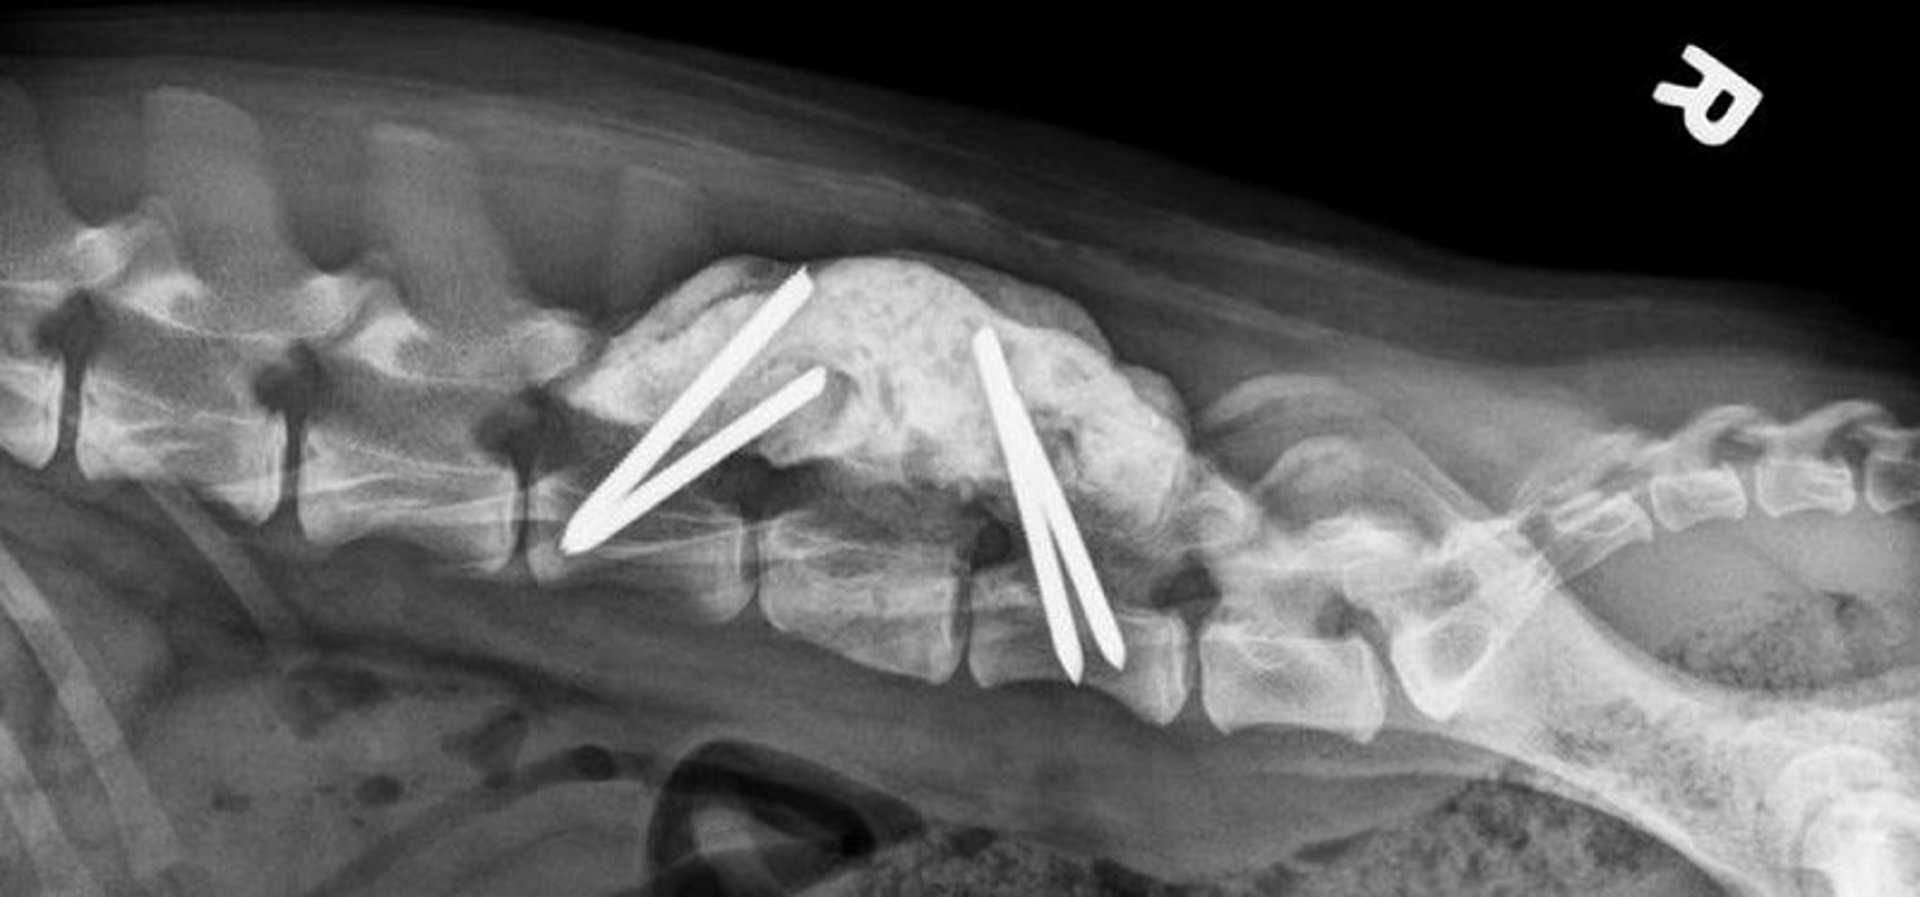

L5 fracture and L5-L6 luxation fixation, dog, 6 weeks after surgery

Postoperative lateral radiographic view of a dog with a fracture of the L5 vertebral body and fixation of L5-L6 luxation. Two fully threaded pins each were placed in the vertebral bodies of L4 and L6. Polymethyl methacrylate was used to connect the four pins. The fracture and luxation are well reduced and healing normally.

Courtesy of Dr. William Thomas.